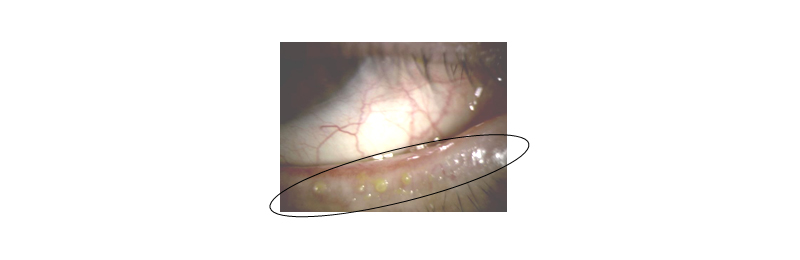

④マイボーム腺機能不全の治療

涙の油層は瞼の上下縁に20~40個あるマイボーム腺という腺から産出されますが、なんらかの原因でマイボーム腺が梗塞するとマイボーム腺機能不全を起こし、その結果涙液の油層がうまく形成されずにドライアイを引き起こします。

ホットタオルで温めたあとに、マイボーム腺梗塞部の処置を行います。加齢が原因で起きますが、若年でもアイメイクが原因で生じたりするので、要注意です。